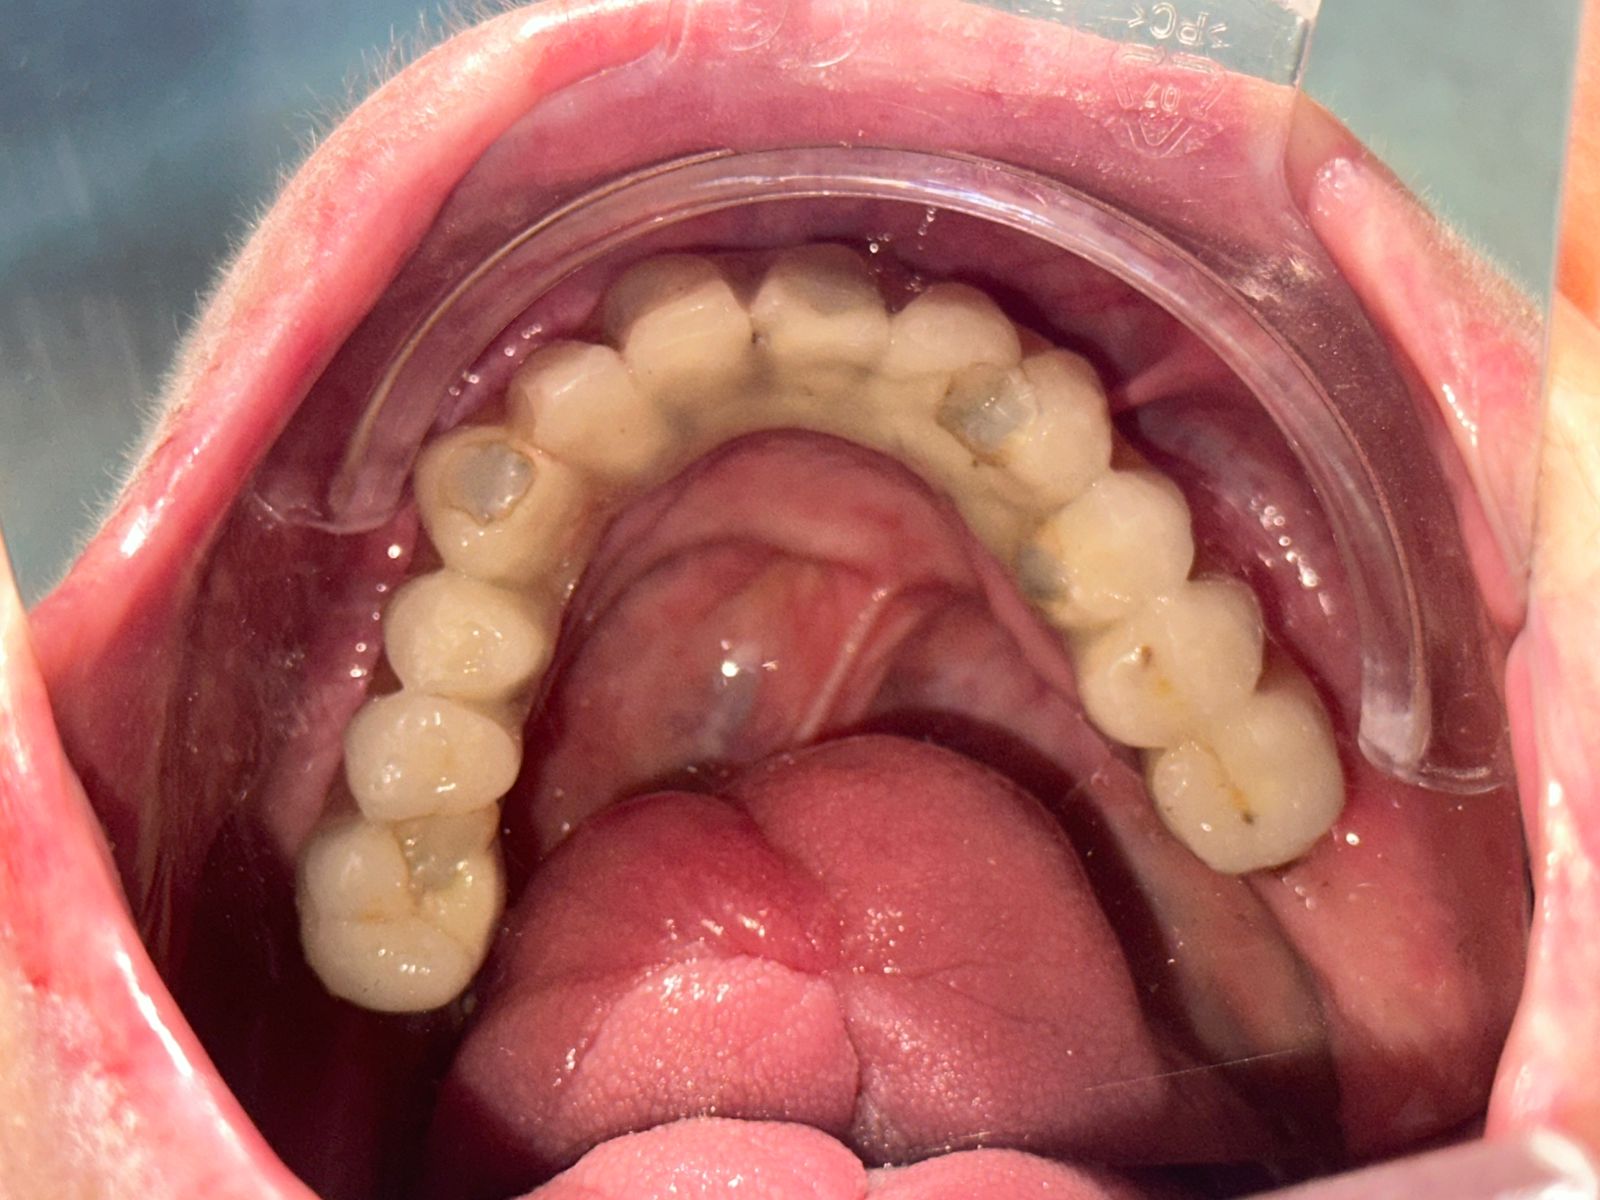

Prezantimi fillestar: një problem që zgjati me vite Pacientja u paraqit në klinikë rreth një vit më parë me një ankesë kryesore: levizshmëri e protezave totale të lëvizshme dhe pamundësi serioze për t’u ushqyer normalisht. Si shumë pacientë që kanë kaluar vite të tëra me proteza të lëvizshme, ajo përjetonte çdo ditë pasiguri, parehati dhe lodhje psikologjike. Ushqimi ishte bërë një proces i vështirë, ndërsa të folurit dhe përtypja shoqëroheshin me frikën se proteza mund të lëvizte apo të binte. Por pas këtij shqetësimi të parë, fshihej një histori shumë më e thellë klinike.

Historia traumatike pas rastit: aksidenti dhe pasojat afatgjata Gjatë anamnezës së detajuar, u evidentua se pacientja kishte pësuar një aksident shumë vite më parë, i cili kishte shkaktuar: Humbje totale të dhëmbëve Krijimin e një komunikimi oronazal (hapje midis kavitetit oral dhe zgavrës nazale) Ky komunikim oronazal nuk ishte vetëm një problem anatomik. Pacientja ndiente kalimin e ajrit përmes kësaj hapjeje, çka ndikonte në frymëmarrje, të folur dhe ndjesinë e përgjithshme të rehatisë. Përveç aspektit funksional, kjo gjendje kishte një peshë të rëndë psikologjike dhe sociale.

rehabilitim total oral mbi implante Pas analizës së plotë, u vendos të realizohej një rehabilitim total i kavitetit oral me: 6 implante dentare në nofullën e sipërme 6 implante dentare në nofullën e poshtme Kurora definitive të mbështetura mbi strukturë të qëndrueshme metalike Ky plan synonte jo vetëm zëvendësimin e dhëmbëve, por rikthimin e funksionit mastikator, stabilitetit, të folurit dhe mbylljen e komunikimit oronazal.